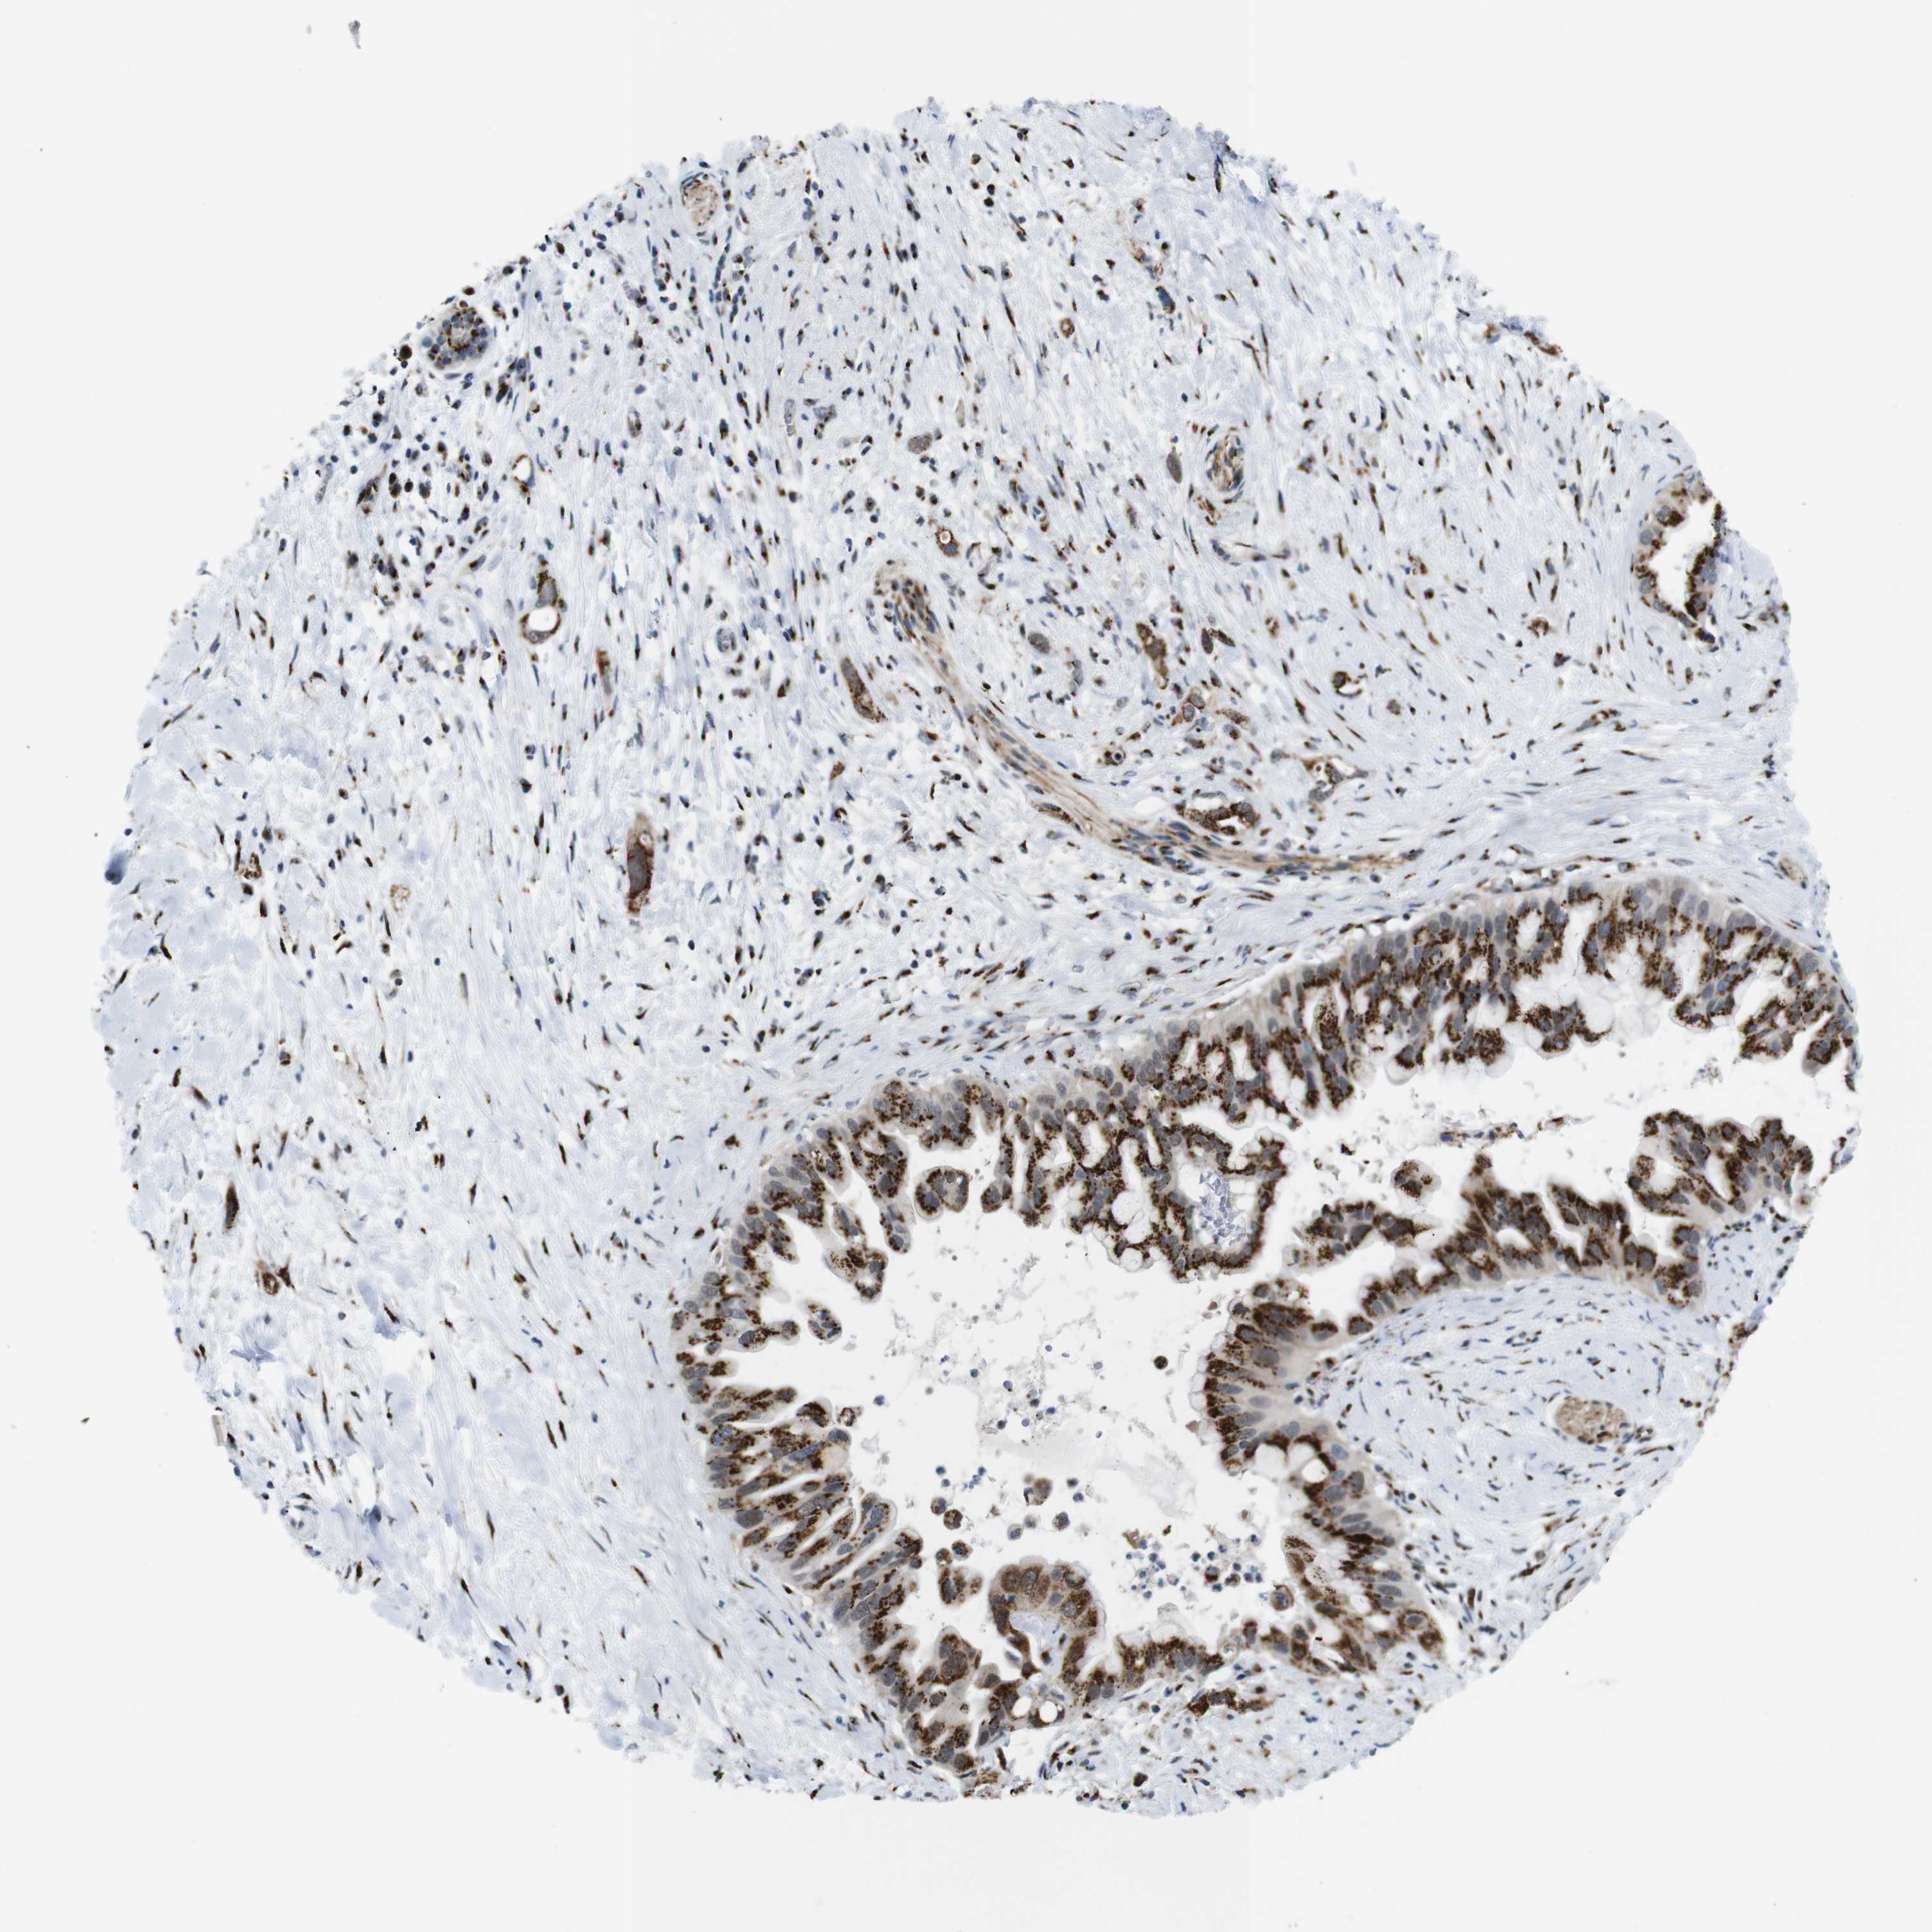

PANCREATIC CANCER - Protein expressioni

A mouse-over function shows sample information and annotation data. Click on an image to view it in a full screen mode. Samples can be filtered based on level of antibody staining by selecting one or several of the following categories: high, medium, low and not detected. The assay and annotation is described here.

Note that samples used for immunohistochemistry by the Human Protein Atlas do not correspond to samples in the TCGA dataset.

Antibody stainingi

Antibody staining in the annotated cell types in the current human tissue is reported as not detected, low, medium, or high, based on conventional immunohistochemistry profiling in selected tissues. This score is based on the combination of the staining intensity and fraction of stained cells.

Each image is clickable and will lead to virtual microscopy that enables deeper exploration of all samples and also displays staining intensity scores, fraction scores and subcellular localization as well as patient and tissue information for each sample.

Antibody HPA012609

Antibody HPA012723

Antibody CAB011489

Staining

High

Medium

Low

Not detected

Intensity

Strong

Moderate

Weak

Negative

Quantity

>75%

75%-25%

<25%

None

Location

Nuclear

Cytoplasmic/membranous

Cytoplasmic/membranous,nuclear

Adenocarcinoma, NOS